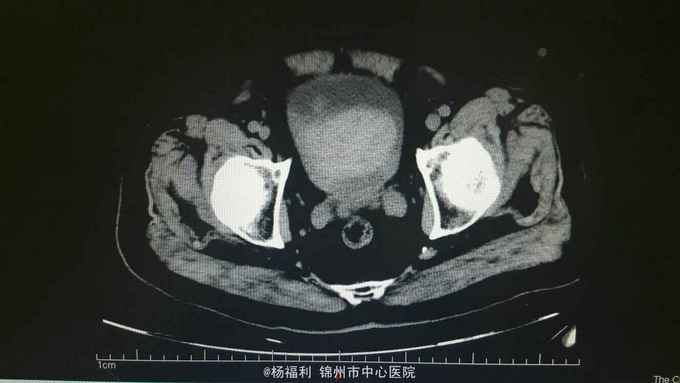

膀胱造瘘管内血尿伴血块,造瘘管周围窦口新鲜肉芽形成。耻骨上隆起,压痛阳性,扣诊浊音。 盆腔ct:见影像资料。内见大量血块。

尿潴留。膀胱内出血。膀胱造瘘术后。 给与患者留置尿管后行膀胱持续冲洗,血尿持续,于膀胱镜下给与患者清除膀胱内血块,发现造瘘口周围膀胱壁出血,滤泡样隆起,病理回报轻度不典型增生。电凝止血后回病房。